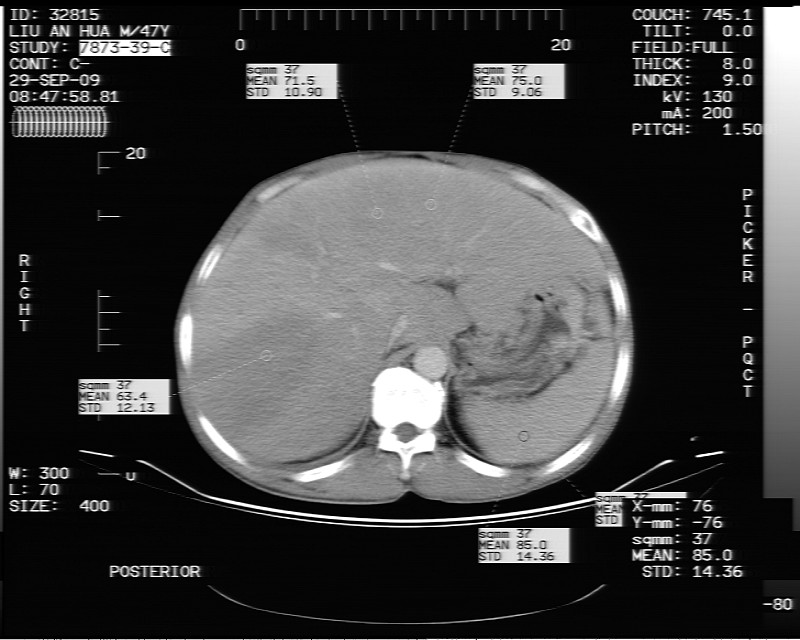

动态增强示:

支持脂肪肝【无占位性,高低密度区同期强化,平扫与强化的密度成比例】

不均匀性脂肪肝。肝脏体积稍大,不除外合并肝功能损害。

不均匀性脂肪肝 。支持!右肾结石

1、不均匀脂肪肝;2、布加氏综合症(肝脏肿大,门脉纤细,下腔海绵状变性,肠系膜上静脉显著扩张)。